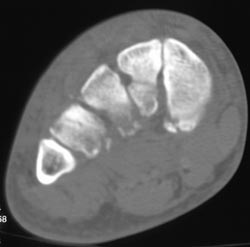

Diagnosis

Congenital Hip Disease With Poor Coverage of Left Femur